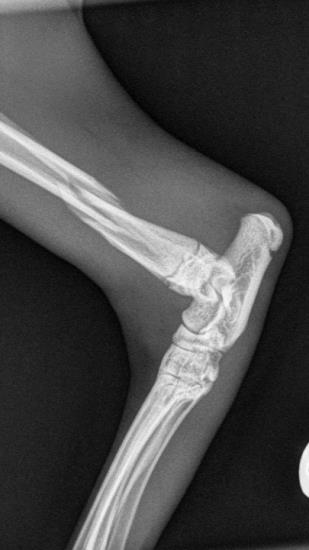

These radiographs show a distal tibial fracture in a six-month cat. Multiple fissure lines can be seen extending towards the distal tibial physis. The tibia is a common site of non-union in the cat and plate failure by bending following tibial fracture stabilisation is reported. In this case, an orthogonal plate has been applied to the cranial aspect of the tibia. This not only allows increased construct stiffness in the sagittal plane but provides for an additional screw fixation point. This can be very useful with distal fractures.